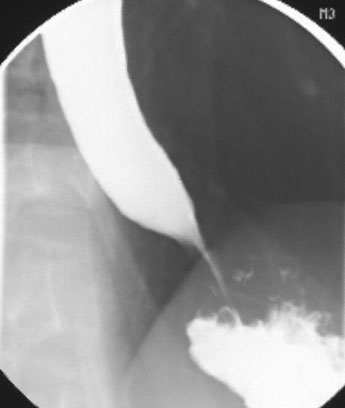

A previously healthy 47-year-old man comes to the physician because of a 3-month history of progressive difficulty swallowing, resulting in a 6-kg (13.2-lb) weight loss. During the past 2 weeks, he has had occasional regurgitation of ingested food. He has not had difficulty breathing or hoarseness. He takes no medications. He does not smoke cigarettes or drink alcohol. His temperature is 37°C (98.6°F), pulse is 75/min, respirations are 18/min, and blood pressure is 122/78 mm Hg. Examination of the neck shows no masses or lymphadenopathy. Cardiopulmonary examination shows no abnormalities. A chest x-ray shows an air-fluid level posterior to the cardiac silhouette. Results of a barium swallow are shown. Esophagogastroduodenoscopy shows esophagitis in the distal esophagus but no stricture or masses. Which of the following is most likely to confirm the diagnosis?